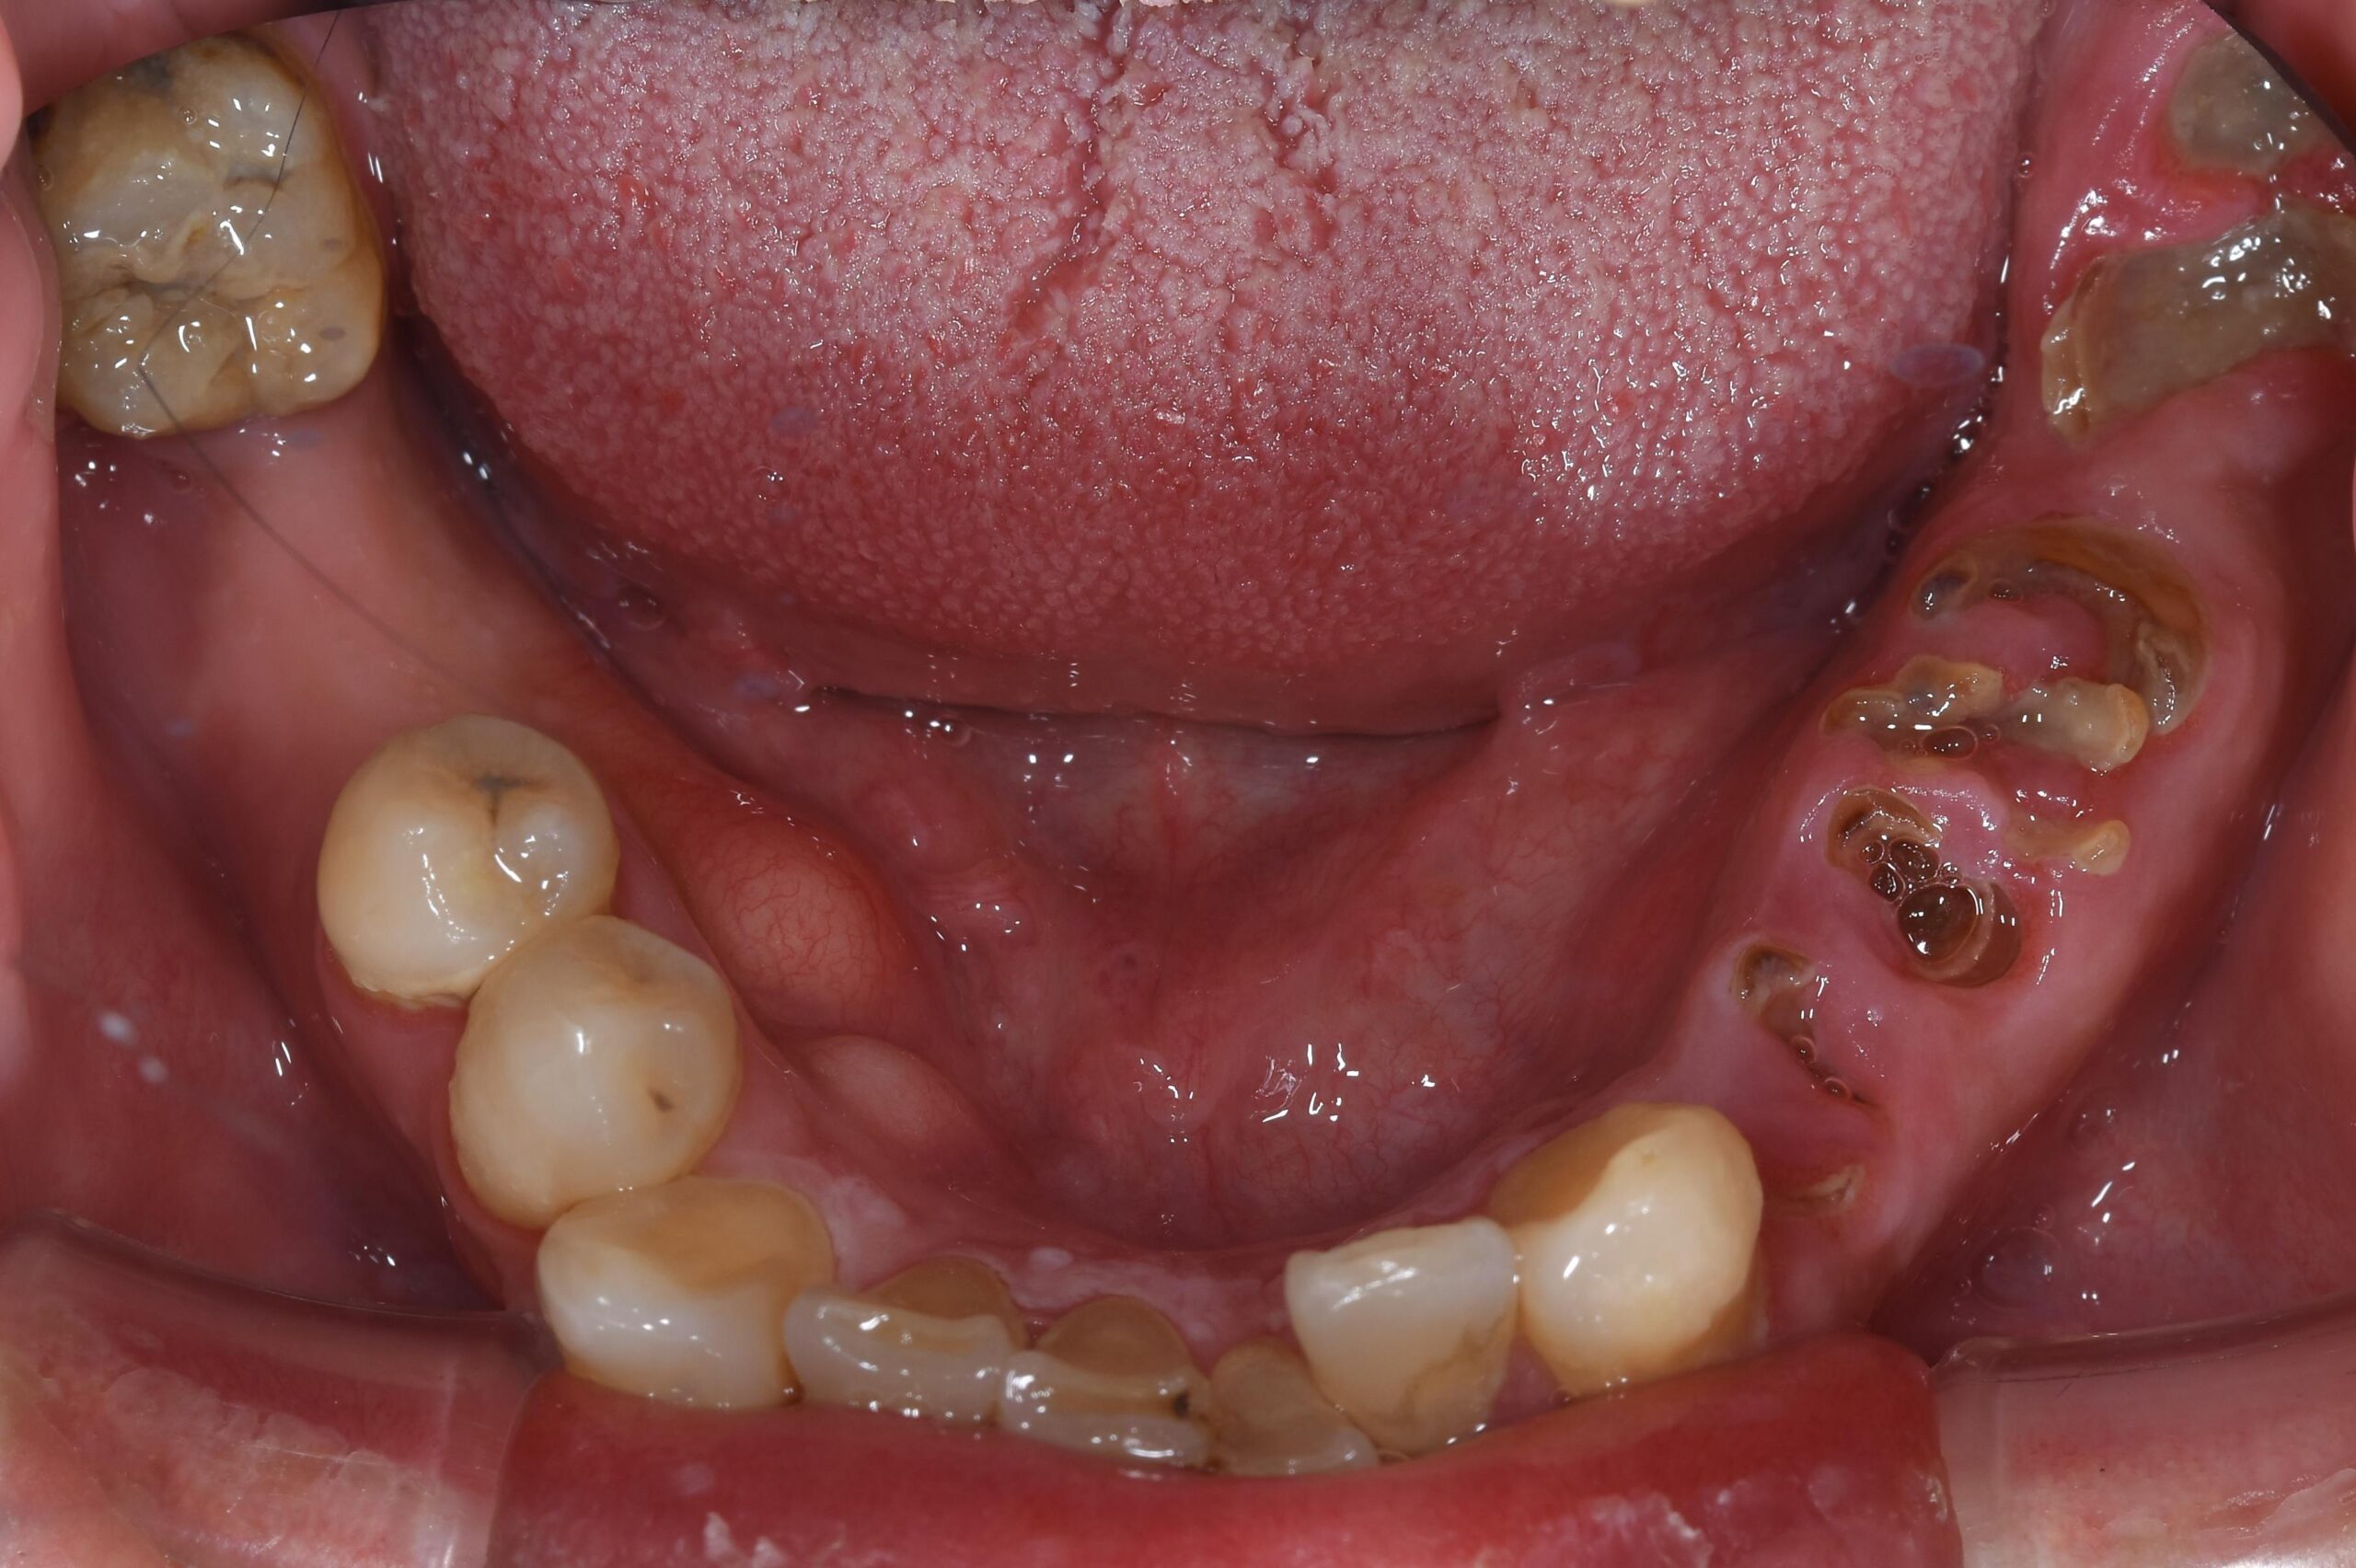

重度虫歯からのインプラント・入れ歯治療(*^-^*)